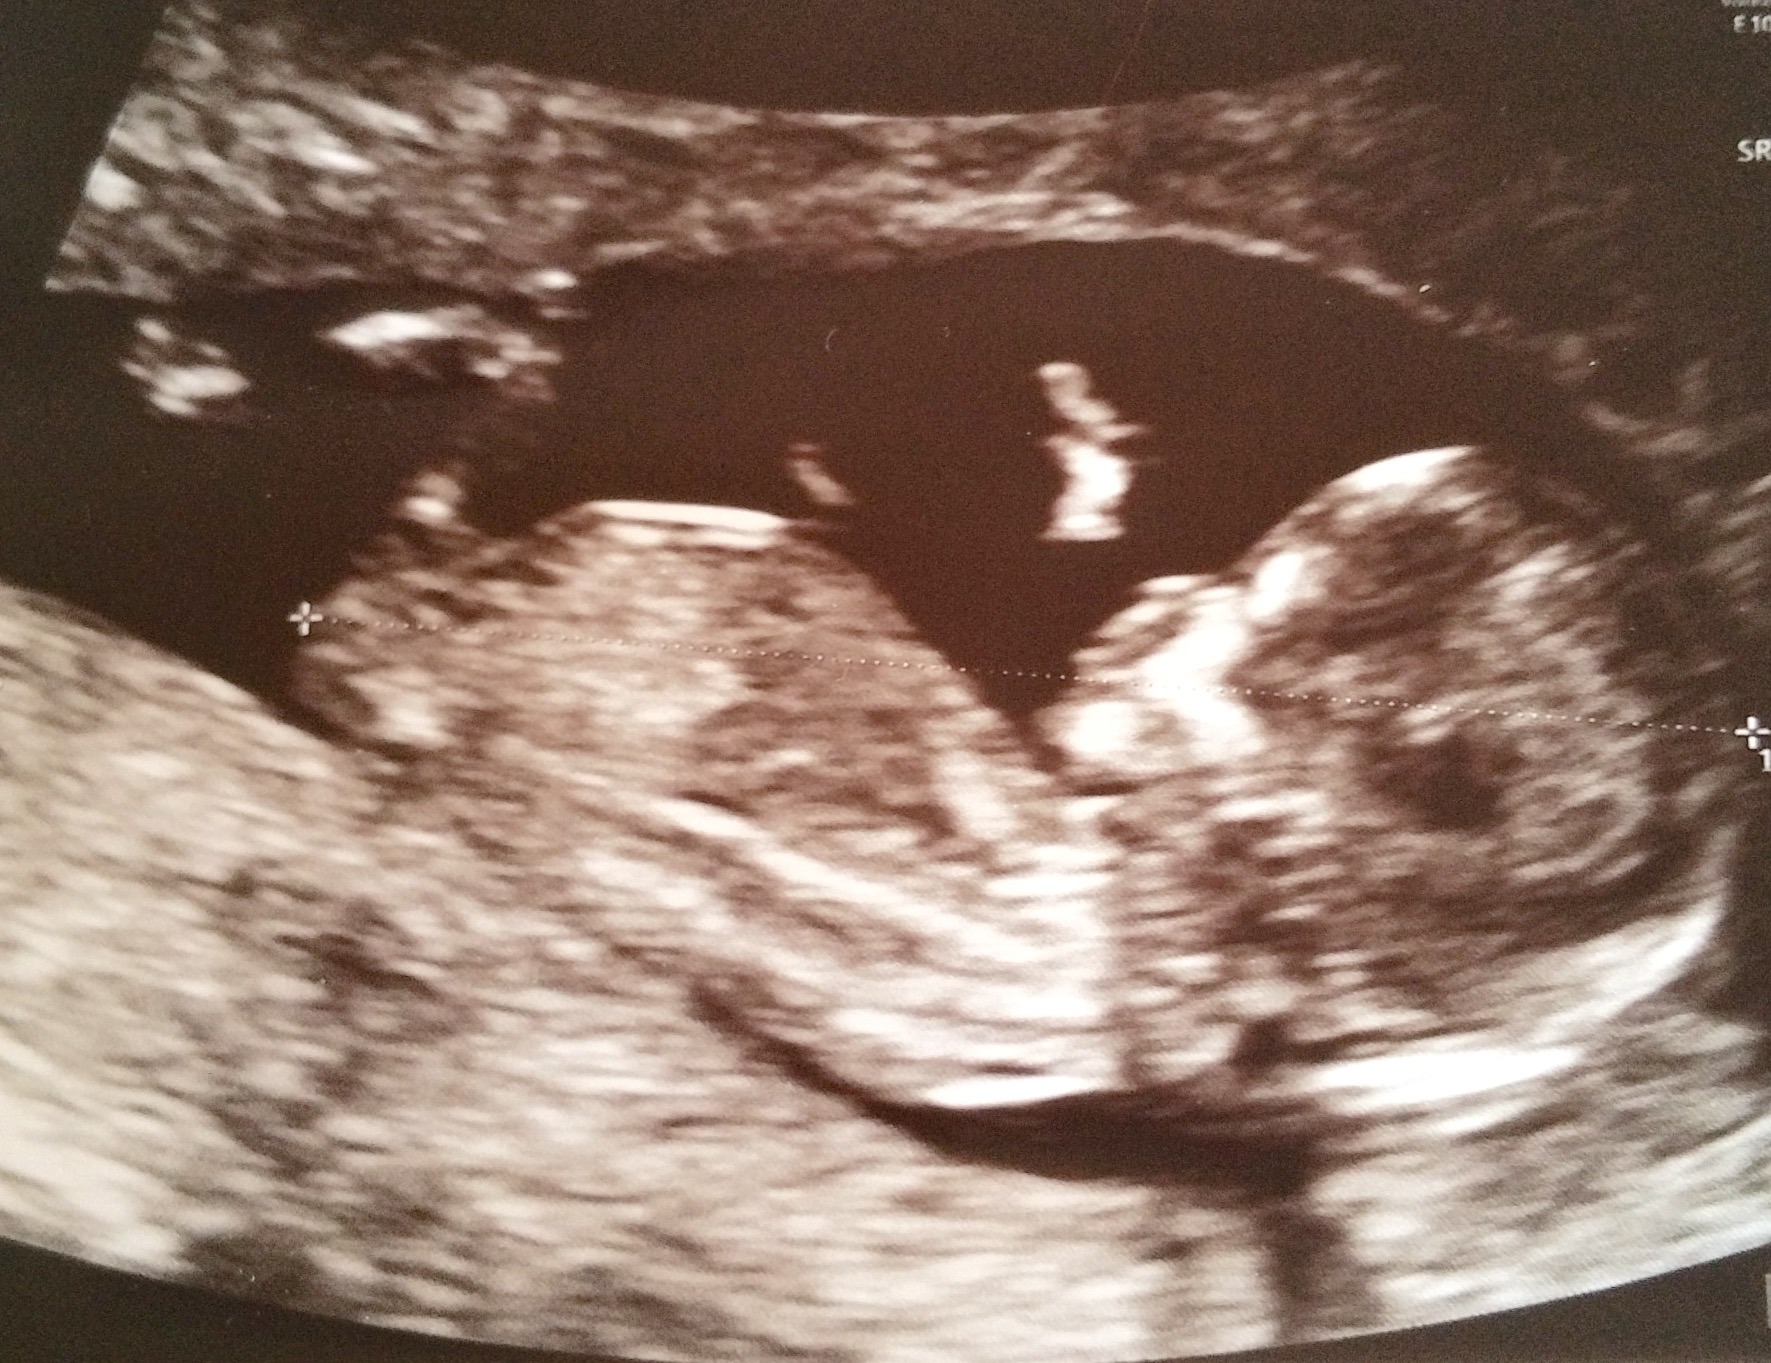

I think the nub looks boyish, but can't tell if it is actually a 'nub' or a leg!

Maybe boy

I'd guess blue x

Don't see a nub sorry. I think that's a leg.

Agree with Ksmom. I think that's a leg.

Can't makeout the nub either

I think that's probably a leg but tentatively guess boy.

I don't think you can tell, I look at it and sometimes I see girl and sometimes I see boy

Leaning boy.

cant see any nub there?!